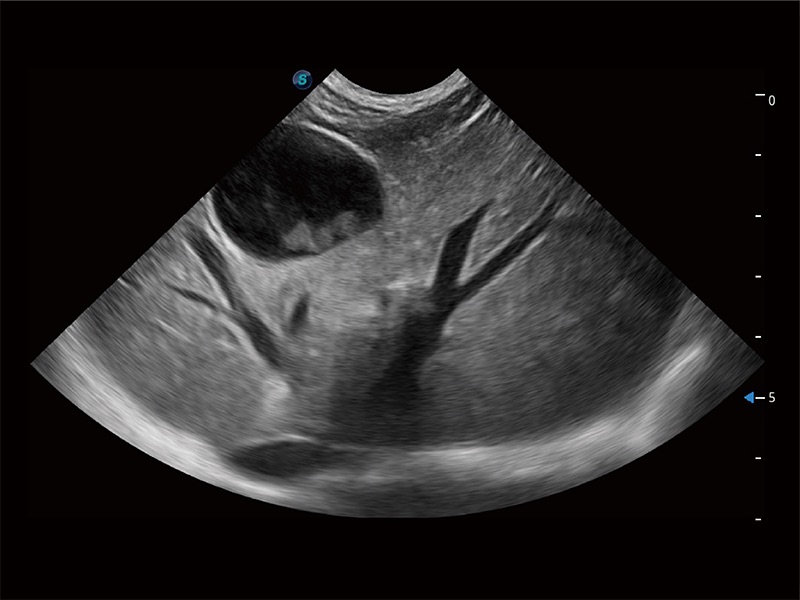

ProPet 80 配备了丰富的心脏探头群、先进的成像技术和专业的心脏测量工具,可帮助动物医生为不同体型和生理结构的动物提供心脏和心肌功能的全面评估。

实时用颜色表示心肌组织运动,观察和定量组织的运动情況,对快速检测与评估心肌的灌注和活性、电传导及心肌收缩和舒张功能等均能提供重要的诊断信息。

通过心肌识别技术与二维斑点追踪技术相结合,对心脏的超声图像进行量化分析。计算心肌17个节段的应变、应变率、速度、位移等,并通过牛眼图的形式进行呈现。

通过360度任意调节3条M型取样线,在同一心动周期上观察心脏不同位置的运动曲线,得到准确的心功能测量数据,有效评估心肌运动及左心室功能。